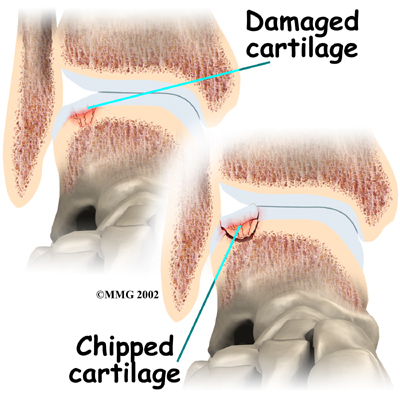

Injury to a joint, such as a bad sprain or fracture, can cause damage to the articular cartilage. The cartilage can be bruised when too much pressure is exerted on it. This damages the cartilage, although if you look at the surface it may not appear to be any different. The injury to the material doesn't show up until months later. Sometimes the cartilage surface is damaged even more severely, and pieces of the cartilage are ripped from the bone. These pieces do not heal back and usually must be removed from the joint surgically. If not, they may float around in the joint, causing the joint to catch and be painful. These fragments of cartilage may also do more damage to the joint surface.

Injury to a joint, such as a bad sprain or fracture, can cause damage to the articular cartilage. The cartilage can be bruised when too much pressure is exerted on it. This damages the cartilage, although if you look at the surface it may not appear to be any different. The injury to the material doesn't show up until months later. Sometimes the cartilage surface is damaged even more severely, and pieces of the cartilage are ripped from the bone. These pieces do not heal back and usually must be removed from the joint surgically. If not, they may float around in the joint, causing the joint to catch and be painful. These fragments of cartilage may also do more damage to the joint surface.

Once this cartilage is ripped away, it does not normally grow back. Unlike bone, holes in the surface are not simply replaced by the cartilage tissue around the hole. Instead the defects are filled with scar tissue. The scar tissue that forms is not nearly as good a material for covering joint surfaces as the cartilage it replaces. It just can't support weight and isn't smooth like true articular cartilage.